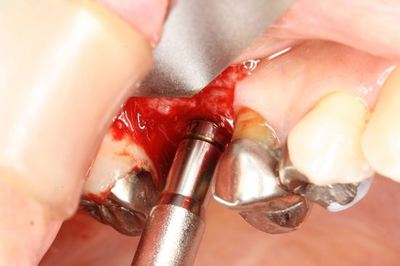

ストローマンインプラント純正のボーンコンデンセーションとオステオトームで

ソケットリフトを行います。

![]()

スムーズに挙上できました。このあとノーズブローテストを行います。